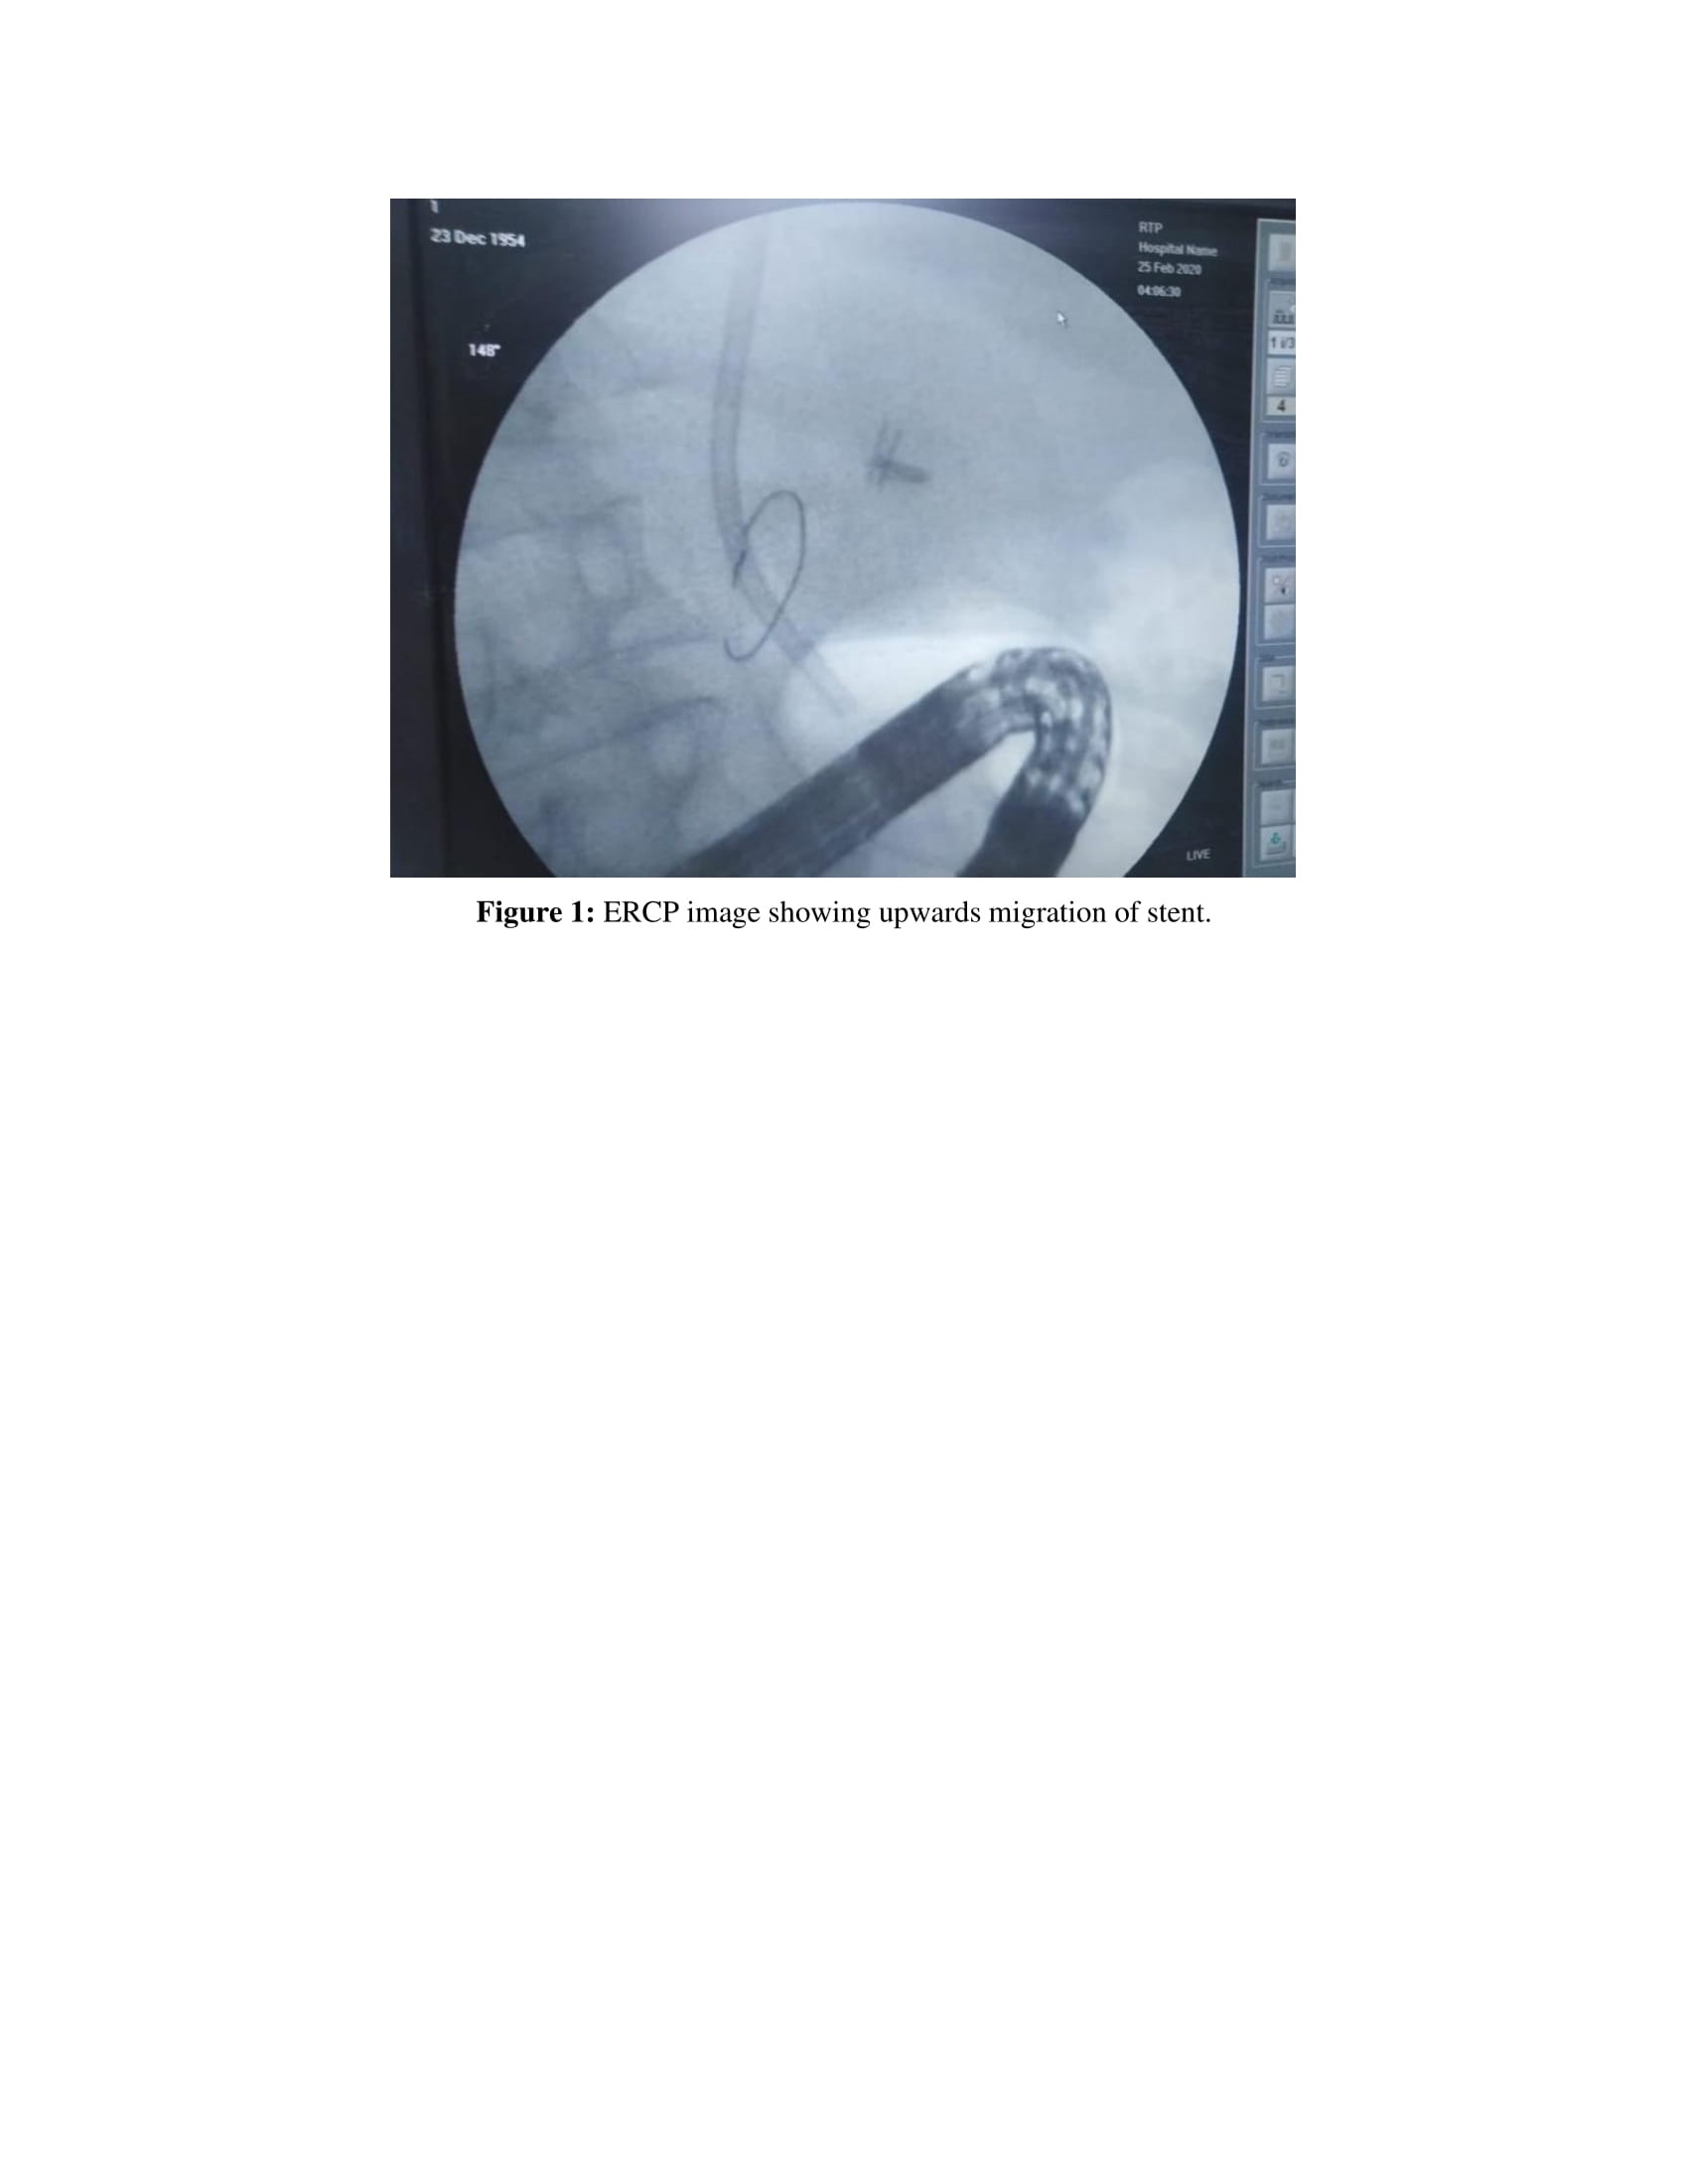

Two days after the second session, total bilirubin was: 37 mg\dL, Direct bilirubin: 29 mg\dL. Follow up abdominal ultrasound showed non functioning stent, ERCP was done with removal of the old upward migrated occluded plastic stent and insertion of a new plastic stent 10 F/10 cm. The patient was kept on antibiotics and follow up; and 3 days after the second ERCP showed, total bilirubin dropped to 15 mg/dL and 10 mg/dL direct bilirubin. Follow up the patient after 1 months revealed a functioning stent with total bilirubin 2 mg/dL. Three months later his labs were 1.2 mg/dl

Our case developed progressive post ERCP cholestasis mostly due to inadequate antibiotic treatment of cholangitis due to premature discharge of the patient from the hospital without receiving the antibiotics. Renal impairment subsequently developed and this markedly worsened the general condition of the patient and threatened his life. The patient was managed with plasma ultrafiltration followed by a drop of the total bilirubin. Unfortunately obstruction of the stent occurred and ERCP was done with stone extraction, extraction of occluded upward migrated stent (Fig. 1). Follow up serum bilirubin was done for 3 months till it came to normal.